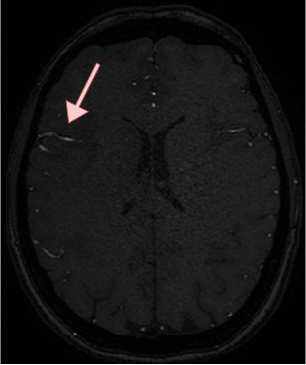

4.4 Qualitative Results

We show sample visual results of representative slices in Figure 3. Sample 3D visual results are given as surface renderings of segmentation maps in Figure 4.

| Baseline GAN | sGAN | Ground Truth | |

|---|---|---|---|

![]() |

|